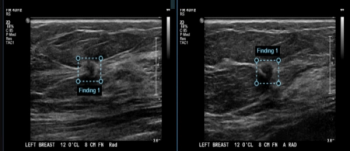

Adjunctive use of an artificial intelligence (AI) software demonstrated nearly equivalent sensitivity and over 28 percent higher accuracy in comparison to radiologist assessment of breast ultrasound images for breast lesions, according to new research presented at the recent Society of Breast Imaging (SBI) conference.